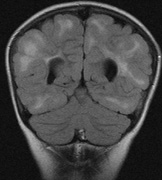

- Cognitive impairment. Thirty percent to 60% of children with NF1 have learning difficulties, which

are typically mild and nonprogressive. These include visual-spatial

problem-solving difficulty, language disorders, and attention

deficit disorder. The reason for this is not clear but may be related

to unidentified bright objects (UBOs) seen on T2-weighted

brain magnetic resonance imaging (MRI) scans. These hyperintensities

are common in young patients with NF1 but decrease with advancing

age. The histopathologic correlate of UBOs is unclear. It has

been postulated that the prevalence of learning difficulties in children

with NF1 may be related to heterozygosity of the NF1 gene (i.e., the gene may have additional functions that affect cognition when the

full complement of its gene product is not expressed in the central nervous

system).25,32–34

In young children, nearly half of sporadic cases fail to meet NIH criteria by 1 year of age, but meet them by age 8 to 12 years. The clinical features appear in the following order: café au lait spots, axillary freckling, Lisch nodules, neurofibromas.26 The inclusion of UBOs on MRI also aids the diagnosis of very young children25 but may require a general anesthetic.